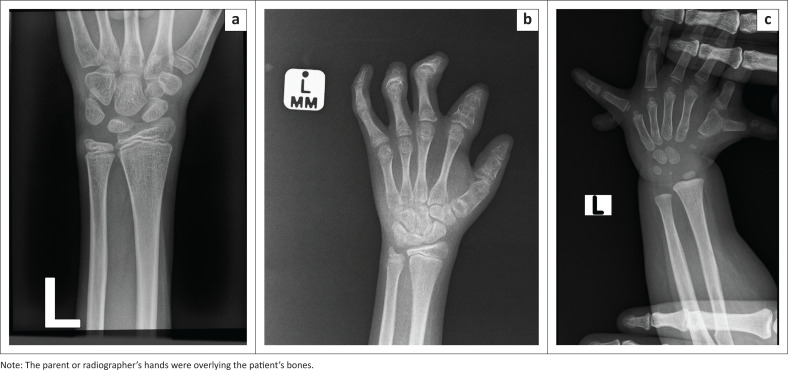

Method: Three manual readers performed manual bone age assessment, and BoneXpert software performed automated bone age assessment on 260 left hand-wrist radiographs. Images where the average of three manual readers (Manual BA) deviated from BoneXpert BA by > 1.5 years, were re-read by an external reader, producing a Reference BA. Manual BA was compared to Carpal BA that was produced by the software. A composite bone age (Comp BA) for the software was defined to estimate the weighting on carpal and tubular bones to achieve the best agreement with Manual BA.